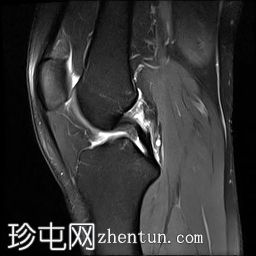

矢状位

斜位PD序列

前交叉韧带(ACL)完全断裂,PDFS和T2加权像显示韧带中部纤维信号增高,残余纤维下垂于胫骨平台,冠状位可见空切迹征。

此外,胫骨平台后外侧和股骨髁前外侧可见骨挫伤异常信号。

外侧副韧带也存在水肿,纤维断裂,提示为III级损伤。

膝关节积液,主要位于髌上囊。

影像学结果显示外侧副韧带III级损伤(完全撕裂),同时伴有前交叉韧带完全撕裂和骨挫伤。

患者随后接受了关节镜手术,手术证实了诊断,并重建了前交叉韧带和外侧副韧带。